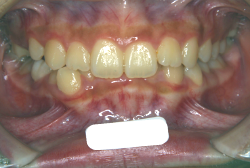

「隙間を閉じたい」という主訴で来院したケースです。診断の結果、「空隙歯列弓+軽度叢生」と判明しましたが、この方の場合は上は隙がある、つまりスペースが余っているのに対して、下は軽度の凸凹がある、つまりスペースが足りないと言う状態でした。

通常、凸凹の症状の場合は、小臼歯を抜歯させていただくのですが、この方の場合は凸凹も軽度で親知らずもないため、非抜歯で対応することになりました。マルチブラケット装置にて治療を開始し、治療期間は11ヶ月でした。治療後は正中の空隙が閉鎖されただけでなく、下の凸凹と下の歯並びの形態そのものが大幅に改善されました。もちろん噛み合わせ的にも正しい状態が確立しています。